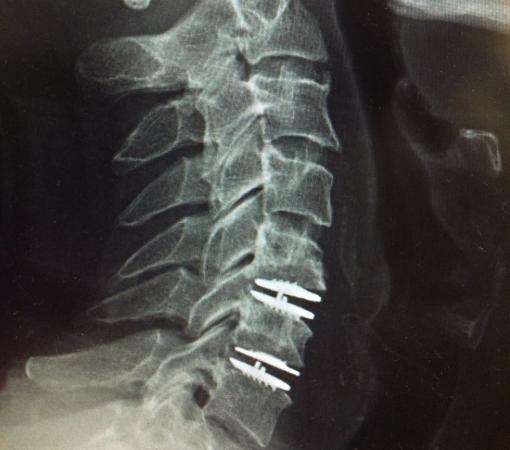

Disc replacement surgery in Mumbai is a minimally invasive procedure where surgeons remove the damaged disc and insert an artificial one. The advanced techniques used at Synapse Spine ensure minimal recovery time and long-term relief.